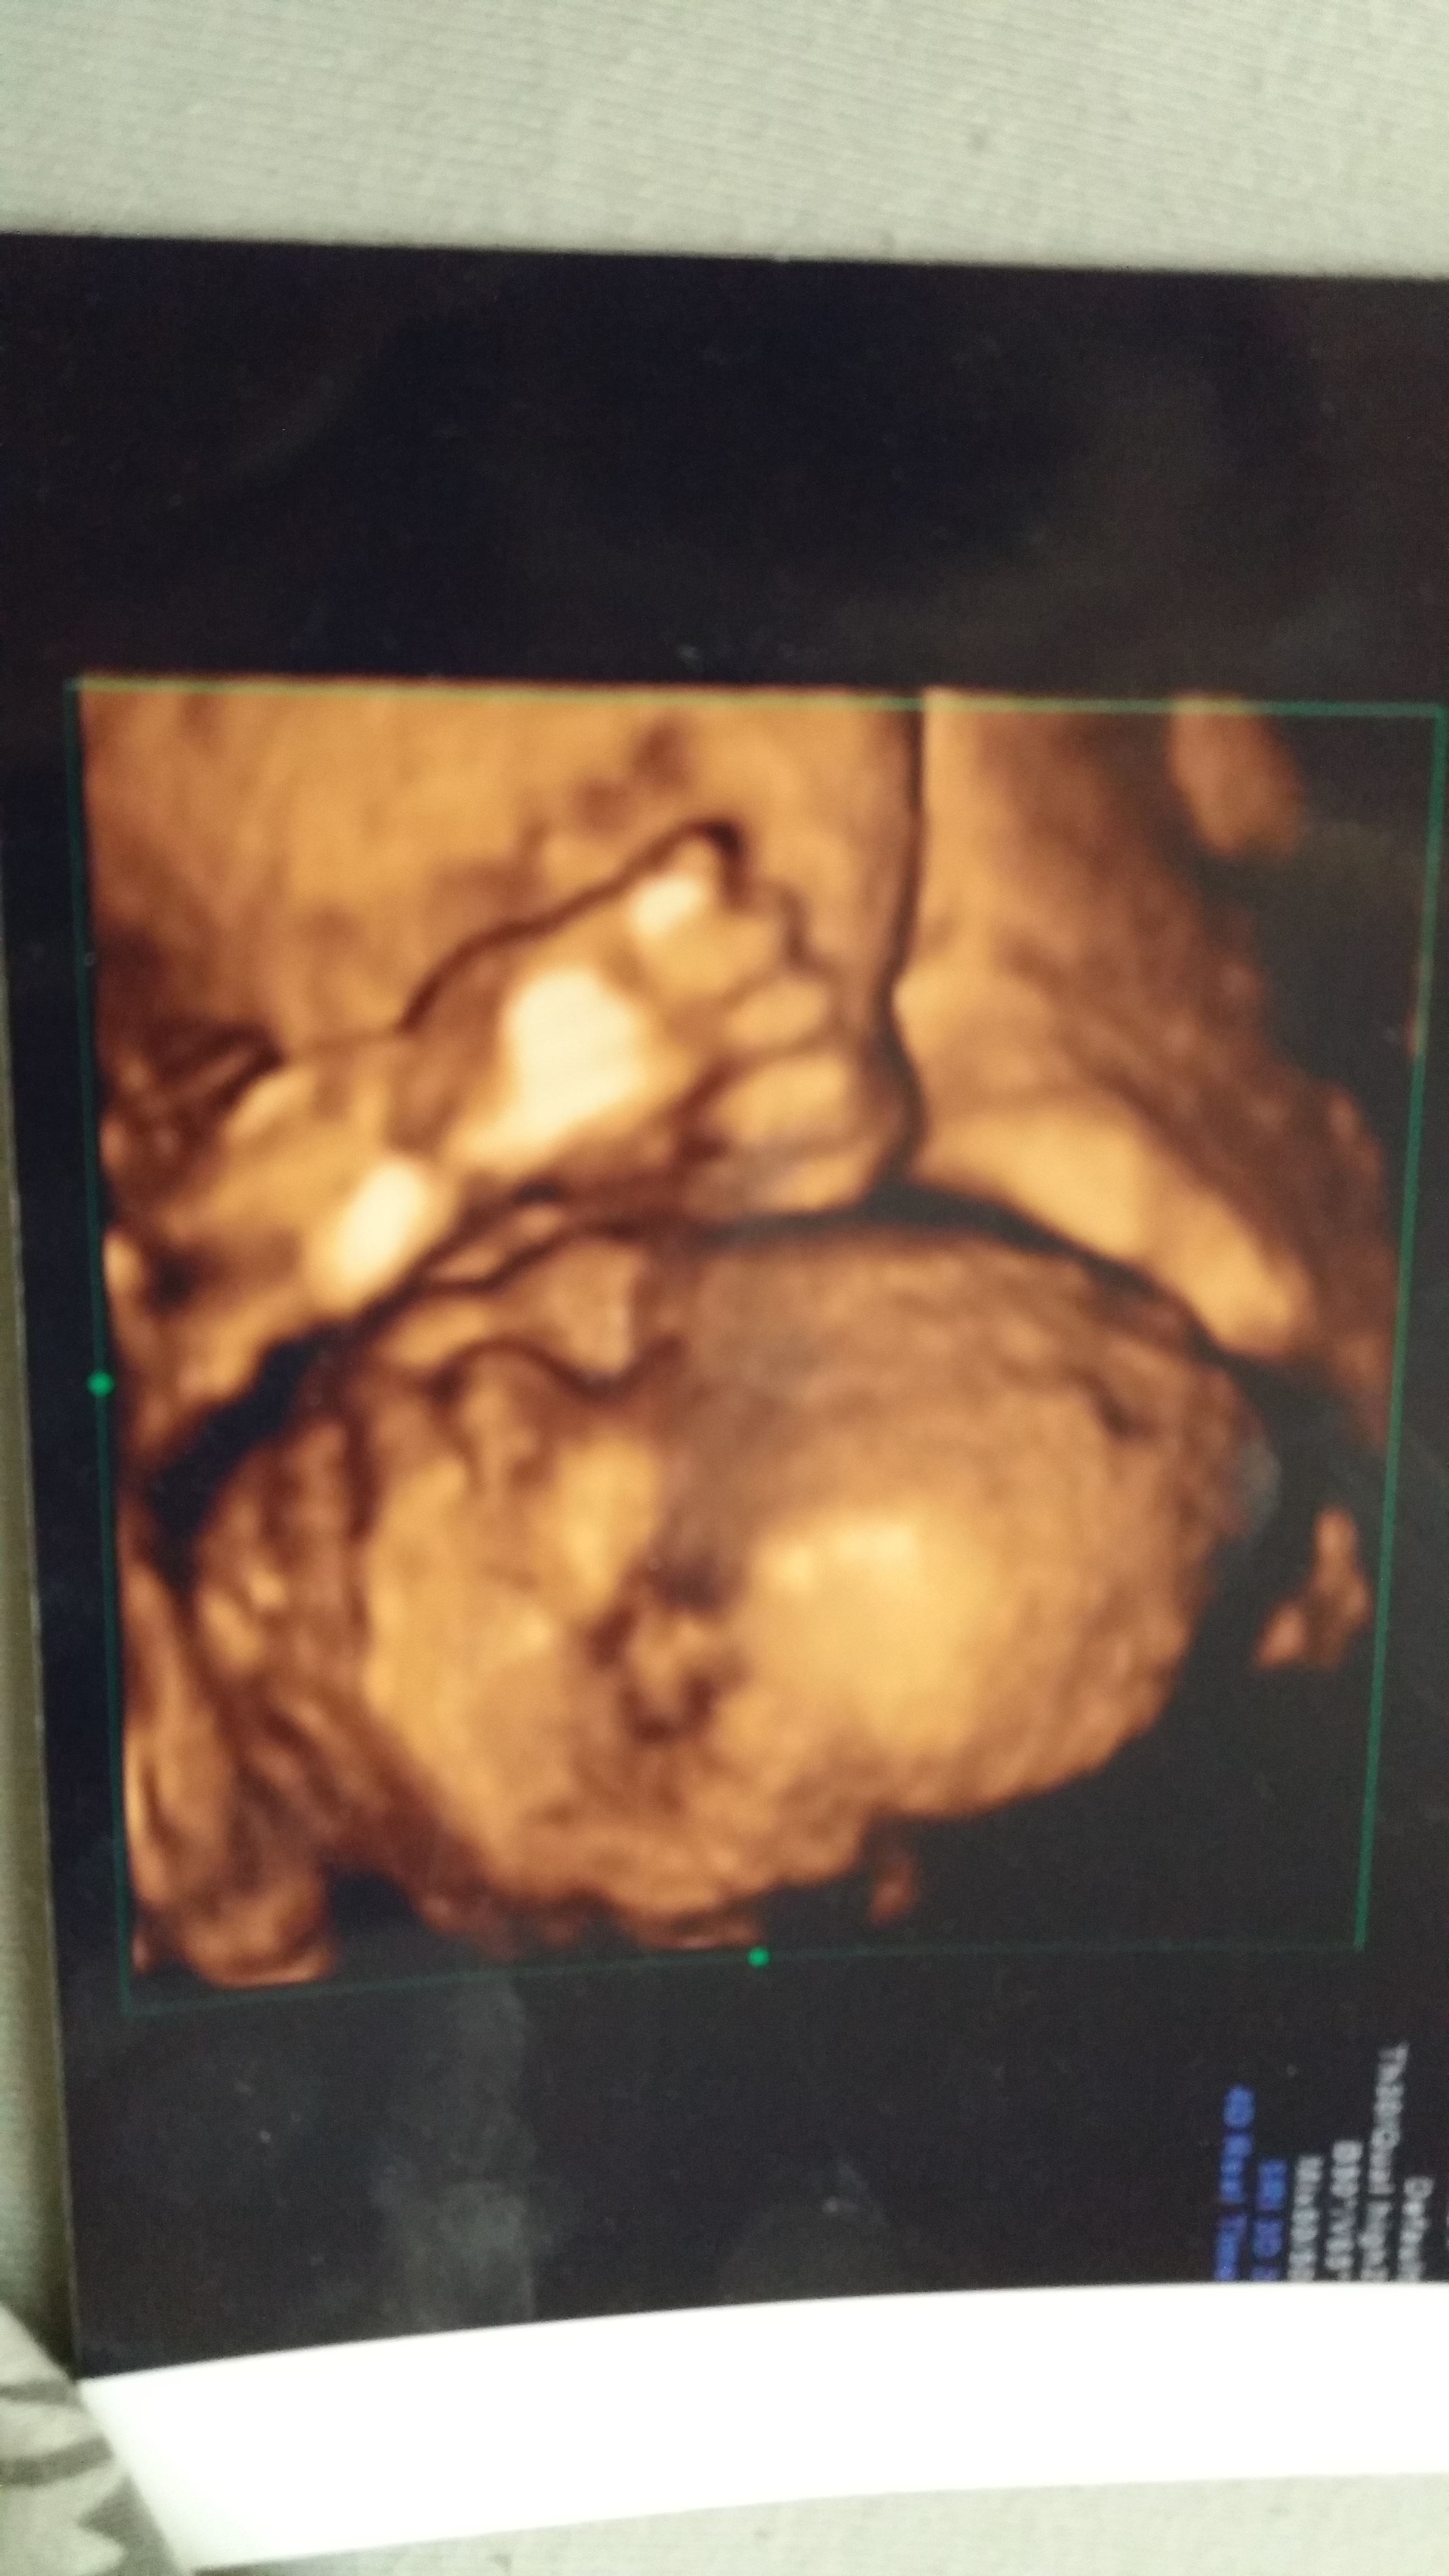

a poza tym teraz mam łożysko na przedniej ścianie i całe dziecko zasłania warstwa łożyska, więc naprawdę musiał się opracować by ująć twarz, nie jest taka jaka powinna ale mówił właśnie ze to przez łożysko.